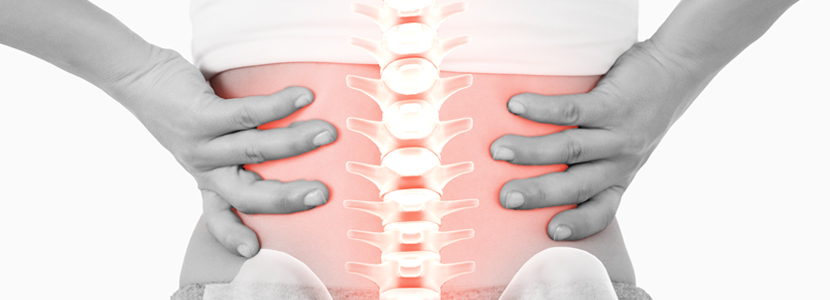

척추관절질환

디스크, 척추협착증

MTS needle을 이용한 치료는 복잡한 여러 원인에 의한 통증을 동시에 다양한 치료방법을 동원하여 치료하기 때문에 다른 치료에 비해 쉽게 치료가 되고, 재발을 잘 하지 않고 만족스럽게 회복될 수 있게 치료합니다.